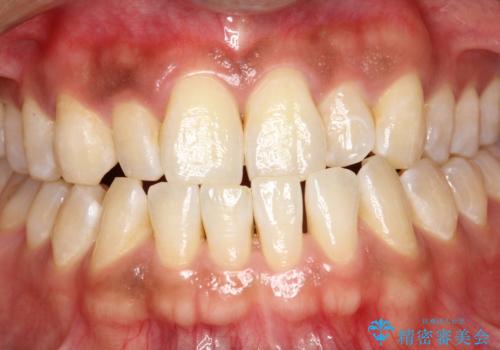

- 歯磨きの際に出血したり、口臭も気になるとのことで来院されました。PMTC30分コースにてクリーニングを行いました。

歯周病の原因は、口の中に棲む歯周菌です。歯周病菌や歯周病菌の出す毒素が引き起こす炎症によって歯茎が腫れ、歯を支えるセメント質、歯槽骨や歯根膜が破壊されて、ついには支えを失った歯が抜けてしまうという怖い病気です。

セルフケアだけでは、歯周病を治したり予防したりすることは困難です。

歯科医院で定期的にクリーニングを行い、歯石除去や細菌に汚染された歯根面の掃除が必要になります。